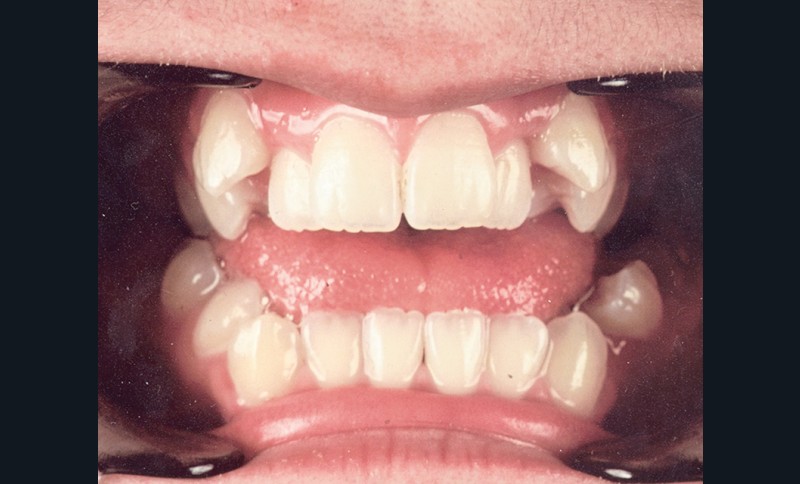

Au niveau squelettique, elle présente une classe I associée à une endognathie maxillaire et une hyperdivergence mandibulaire majeure liée à un excès de croissance alvéolaire verticale postérieure maxillaire et une inclinaison mandibulaire très marquée (fig. 1 et 3).

Sur le plan occlusal et dentaire, on observe une classe I molaire, une occlusion transversale en bout à bout à droite et inversée à gauche et une béance antérieure sévère s’étendant jusqu’aux molaires. Un encombrement est présent aux deux arcades avec des dystopies canines importantes (fig. 2).